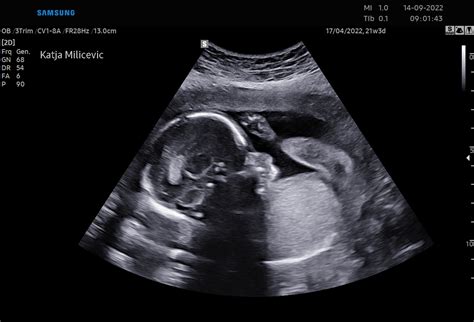

Prva misel vizualne umetnice Samire Kentrić ob pogledu na fotografijo Simone Semenič pa je bila: "O, kako fina ideja. Spustimo novo noter (v državo) in hkrati tudi ven (iz telesa)!" Kadar pa umetniški ideji uspe prebuditi tako intenzivne odzive, lahko avtorici le čestitamo, meni Kentrićeva. Pri tem sta se umetnici sklicevali na umetniško svobodo in odklonili konkretnejše pojasnjevanje svojega dela.